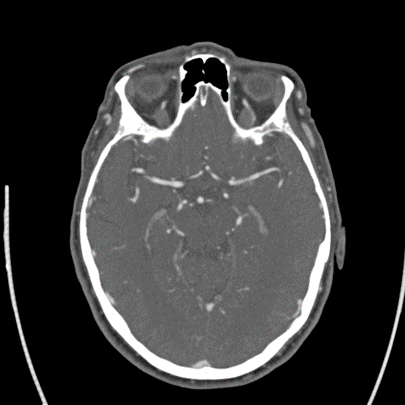

2/ Elderly person with #HTN #HLD ๐Ÿšฌ who wakes up with R-sided weakness, mild aphasia, NIHSS 8 at outside ๐Ÿฅ. ๐Ÿšซ lytics as wake-up, but CT with #denseMCA and CTA with a left M1 non occlusive thrombus. Transferred for #thrombectomy evaluation. Imaging as follows:

3/ On arrival, NIHSS now 3 for R drift, ๐Ÿ˜•, no aphasia. #CTP as below. CT still with #ASPECTS 9: